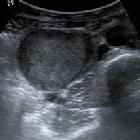

The organs of Zuckerkandl are not often visualized radiologically unless they are involved in a pathologic process, including:

- extraadrenal pheochromocytoma based in organ of Zuckerkandl

- Paragangliom des Retroperitoneums